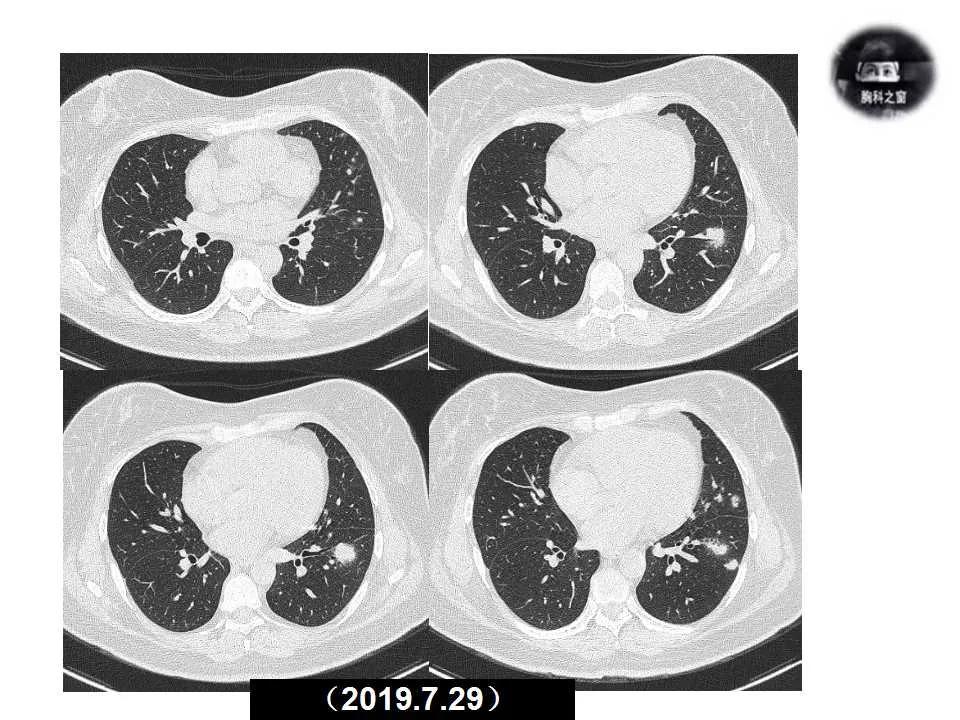

主诉:发现左肺病变1天

现病史:患者1天前体检胸部CT提示左肺病变,之前一段时间进食较少,七月初、七月中旬出现咳嗽、胸痛、无法深呼吸,无咯血,无乏力、盗汗,无明显体重减轻,为接受进一步诊治收入院。(2019.7.30)

影像诊断:真菌性肺炎,隐球菌可能性大。

追问病史,有近距离接触鸽子史。隐球菌抗原(+)。

肺隐球菌病